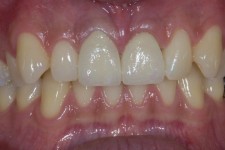

LIJEVO: 1a početno stanje,prednji zubi - DESNO: 1b nakon završetka terapijee LIJEVO: 2a revizija punjenja korijenskih kanala,višekorijenski zubi        <br />